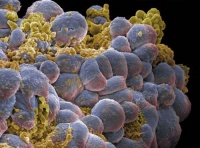

卵巢癌的病理改变[编辑 | 编辑源代码]

卵巢肿瘤卵巢癌病理改变的分类方法很多,本章采纳以组织发生为依据而有临床实用意义的分类。

(一)胚上皮副中肾体腔上皮)来源的卵巢恶性肿瘤 如浆液性腺癌、粘液性腺癌、子宫内膜样腺癌、混合性浆液粘液性囊腺癌、纤维腺癌、恶性勃勒纳氏瘤、副中肾透明细胞癌、未分化(间变性)癌等,这些肿瘤有时有黄素化作用。